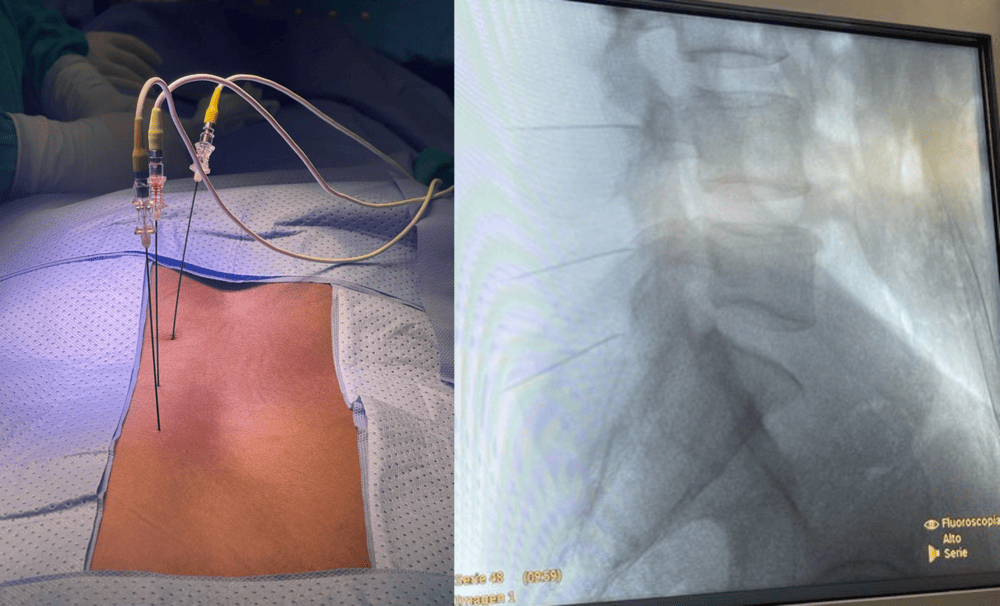

• Procedimiento: Se realiza en quirófano, con sedación ligera y control por fluoroscopia. Se introduce una aguja con sensor en la punta sobre cada articulación afectada. Se realizan comprobaciones sensitivas y motoras antes de la radiofrecuencia.

• Puede realizarse en toda la columna (cervical, dorsal, lumbar, sacra) y ser unilateral o bilateral. La mejoría suele ser inmediata, aunque puede tardar hasta 4 semanas. Es una técnica segura con bajas complicaciones, aunque puede haber dolor o molestias en la zona, o neuralgia temporal (sensación de quemazón o disestesias que mejoran en 4-8 semanas).